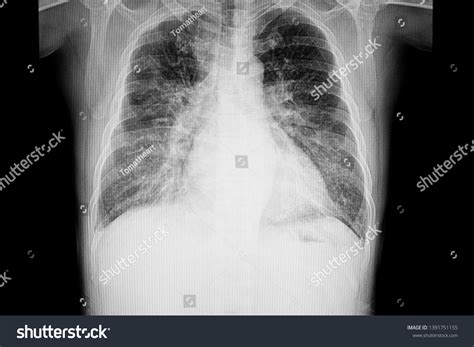

When a patient presents to the emergency department with acute respiratory distress, rapid diagnostic imaging becomes a cornerstone of clinical decision-making. Among the various tools available to physicians, the Pulmonary Edema Cxr (chest X-ray) remains the most frequently ordered and clinically significant diagnostic exam. Understanding the classic radiographic patterns of pulmonary edema is essential for medical professionals, as this condition represents a life-threatening accumulation of fluid in the pulmonary interstitial and alveolar spaces, often secondary to congestive heart failure or other systemic pathologies.

The Pulmonary Edema Cxr is highly sensitive for identifying fluid overload, though it requires a keen eye to differentiate between cardiogenic and non-cardiogenic causes. Radiologists and clinicians look for specific markers that indicate increased capillary hydrostatic pressure or altered vascular permeability. When evaluating a chest X-ray for this condition, the focus is placed on vascular prominence, redistribution of blood flow, and the presence of interstitial or alveolar opacities.

Key radiographic signs often appear in a specific sequence as the severity of the fluid overload progresses. Identifying these early can prevent the escalation to severe respiratory failure. The hallmark appearance is often referred to as "pulmonary congestion," which describes the initial phase of fluid accumulation.

There is a standardized progression of findings visible on a Pulmonary Edema Cxr. Recognizing these patterns allows for a systematic approach to diagnosis. The following findings are commonly documented in clinical reports:

• Cephalization: The redistribution of pulmonary blood flow to the upper lobes, which is one of the earliest signs of increased pulmonary venous pressure.

• Kerley B Lines: These are short, horizontal lines perpendicular to the pleural surface at the lung bases, representing thickened interlobular septa due to interstitial edema.

• Peribronchial Cuffing: This appears as a thickening of the bronchial walls, giving them a "donut" or "cuff-like" appearance on cross-section.

• Pleural Effusions: Fluid collecting in the pleural space, often bilateral but potentially unilateral, commonly seen in congestive heart failure.

• Bat-wing Opacities: In more severe cases, bilateral central alveolar opacities sparing the periphery of the lungs, indicating profound alveolar flooding.